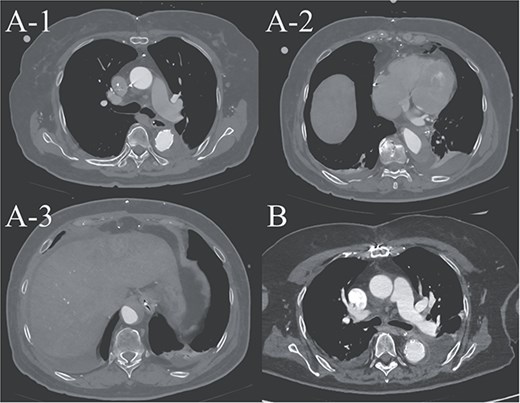

Preoperative contrast-enhanced CT images. (A) Stanford type A acute aortic dissection with the primary entry tear extending from the ascending aorta to the aortic arch, showing a patent false lumen. (B) Three-dimensional reconstructed image.

A 70-year-old woman presented to the emergency department with sudden-onset chest and back pain. Contrast-enhanced CT revealed an ATAAD extending from the ascending aorta to the bilateral common iliac arteries. The primary entry tear extended from the ascending aorta into the aortic arch, and the false lumen remained patent throughout its entire peripheral extent (Fig. 1). Both renal arteries originated from the true lumen, and there was no malperfusion. Vital signs were stable, and the patient was not in shock. The patient underwent emergency total arch replacement with FET implantation using a 27 × 90 mm FROZENIX four-branched graft (Japan Lifeline Co., Ltd, Tokyo, Japan). The procedure was completed in 7 h and 6 min without intraoperative complications. Postoperatively, urine output declined markedly. Serum creatinine increased from a baseline of 0.81 to 2.61 mg/dl on postoperative Day 1. Diuretics failed to improve urine output, and renal replacement therapy was initiated. Contrast-enhanced CT on postoperative Day 2 showed no signs of renal malperfusion. Although the renal medulla exhibited normal enhancement, a diffuse non-enhancing area throughout the renal cortex—referred to as the “reverse rim sign”—was observed, consistent with RCN (Fig. 2). Thrombosis of the false lumen in the descending thoracic and thoracoabdominal aorta had progressed (Fig. 3). The patient developed persistent coagulopathy, with sustained hypofibrinogenemia and thrombocytopenia. On postoperative Day 2, the platelet count was 4.1 × 104/μl, D-dimer 13.5 μg/ml, and PT-INR 1.54, yielding an International Society on Thrombosis and Hemostasis DIC score of 6, consistent with overt DIC. Anticoagulation therapy with heparin and warfarin was administered. Ultimately, by postoperative Day 50, a total of 36 units of fresh frozen plasma and 100 units of platelets had been transfused; however, coagulation parameters gradually normalized thereafter, and no further transfusions were required (Fig. 4). A follow-up CT on postoperative Day 21 demonstrated further remodeling of the thrombosed false lumen. Brain magnetic resonance imaging performed on postoperative Day 9 to investigate delayed emergence revealed multiple scattered small acute ischemic infarctions involving the cerebellum, brainstem, and cerebral cortex (Fig. 5). These were not attributed to large-vessel occlusion but rather to systemic microthrombotic emboli. Despite supportive care, renal function did not recover, and maintenance dialysis was initiated. The patient was transferred to another hospital on postoperative Day 182.

(A-1–3) contrast-enhanced CT image acquired on postoperative Day 2, showing advanced false lumen thrombosis. (B) Contrast-enhanced CT image acquired on postoperative Day 21, demonstrating further remodeling of the false lumen. This image is at approximately the same level as A-1, and the false lumen's thickness is clearly reduced.